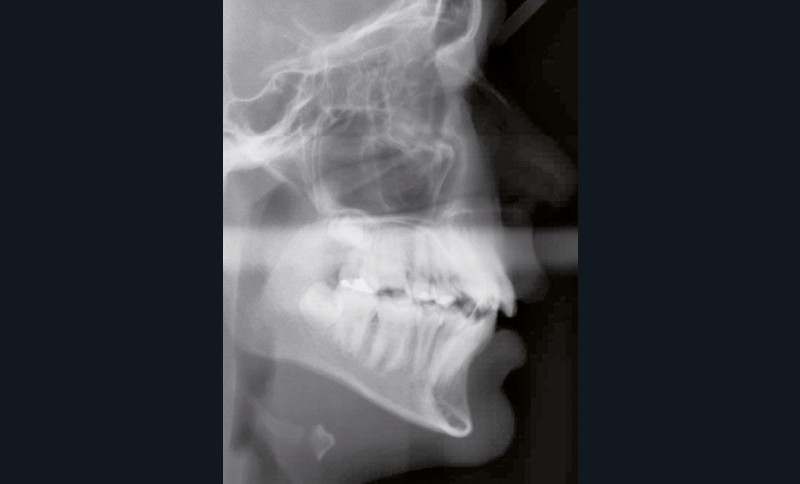

En denture adulte, la DDM est majeure avec un déficit de place estimé de 13 mm à la mandibule. Les lésions carieuses ont aussi touché les premières molaires permanentes maxillaires. La 26 a été avulsée et la 27 a pris sa place. Côté controlatéral, la 16 est fortement délabrée, rendant impossible sa conservation. Les molaires ayant plus mésialé à l’arcade mandibulaire, les rapports occlusaux sont de classe III. Les incisives sont versées vers l’avant, mais nous pouvons considérer qu‘il s’agit d’une biproalvéolie ethnique. Du point de vue squelettique, le patient présente une classe II squelettique par rétromandibulie sur un schéma facial hyperdivergent (fig. 1a-j).